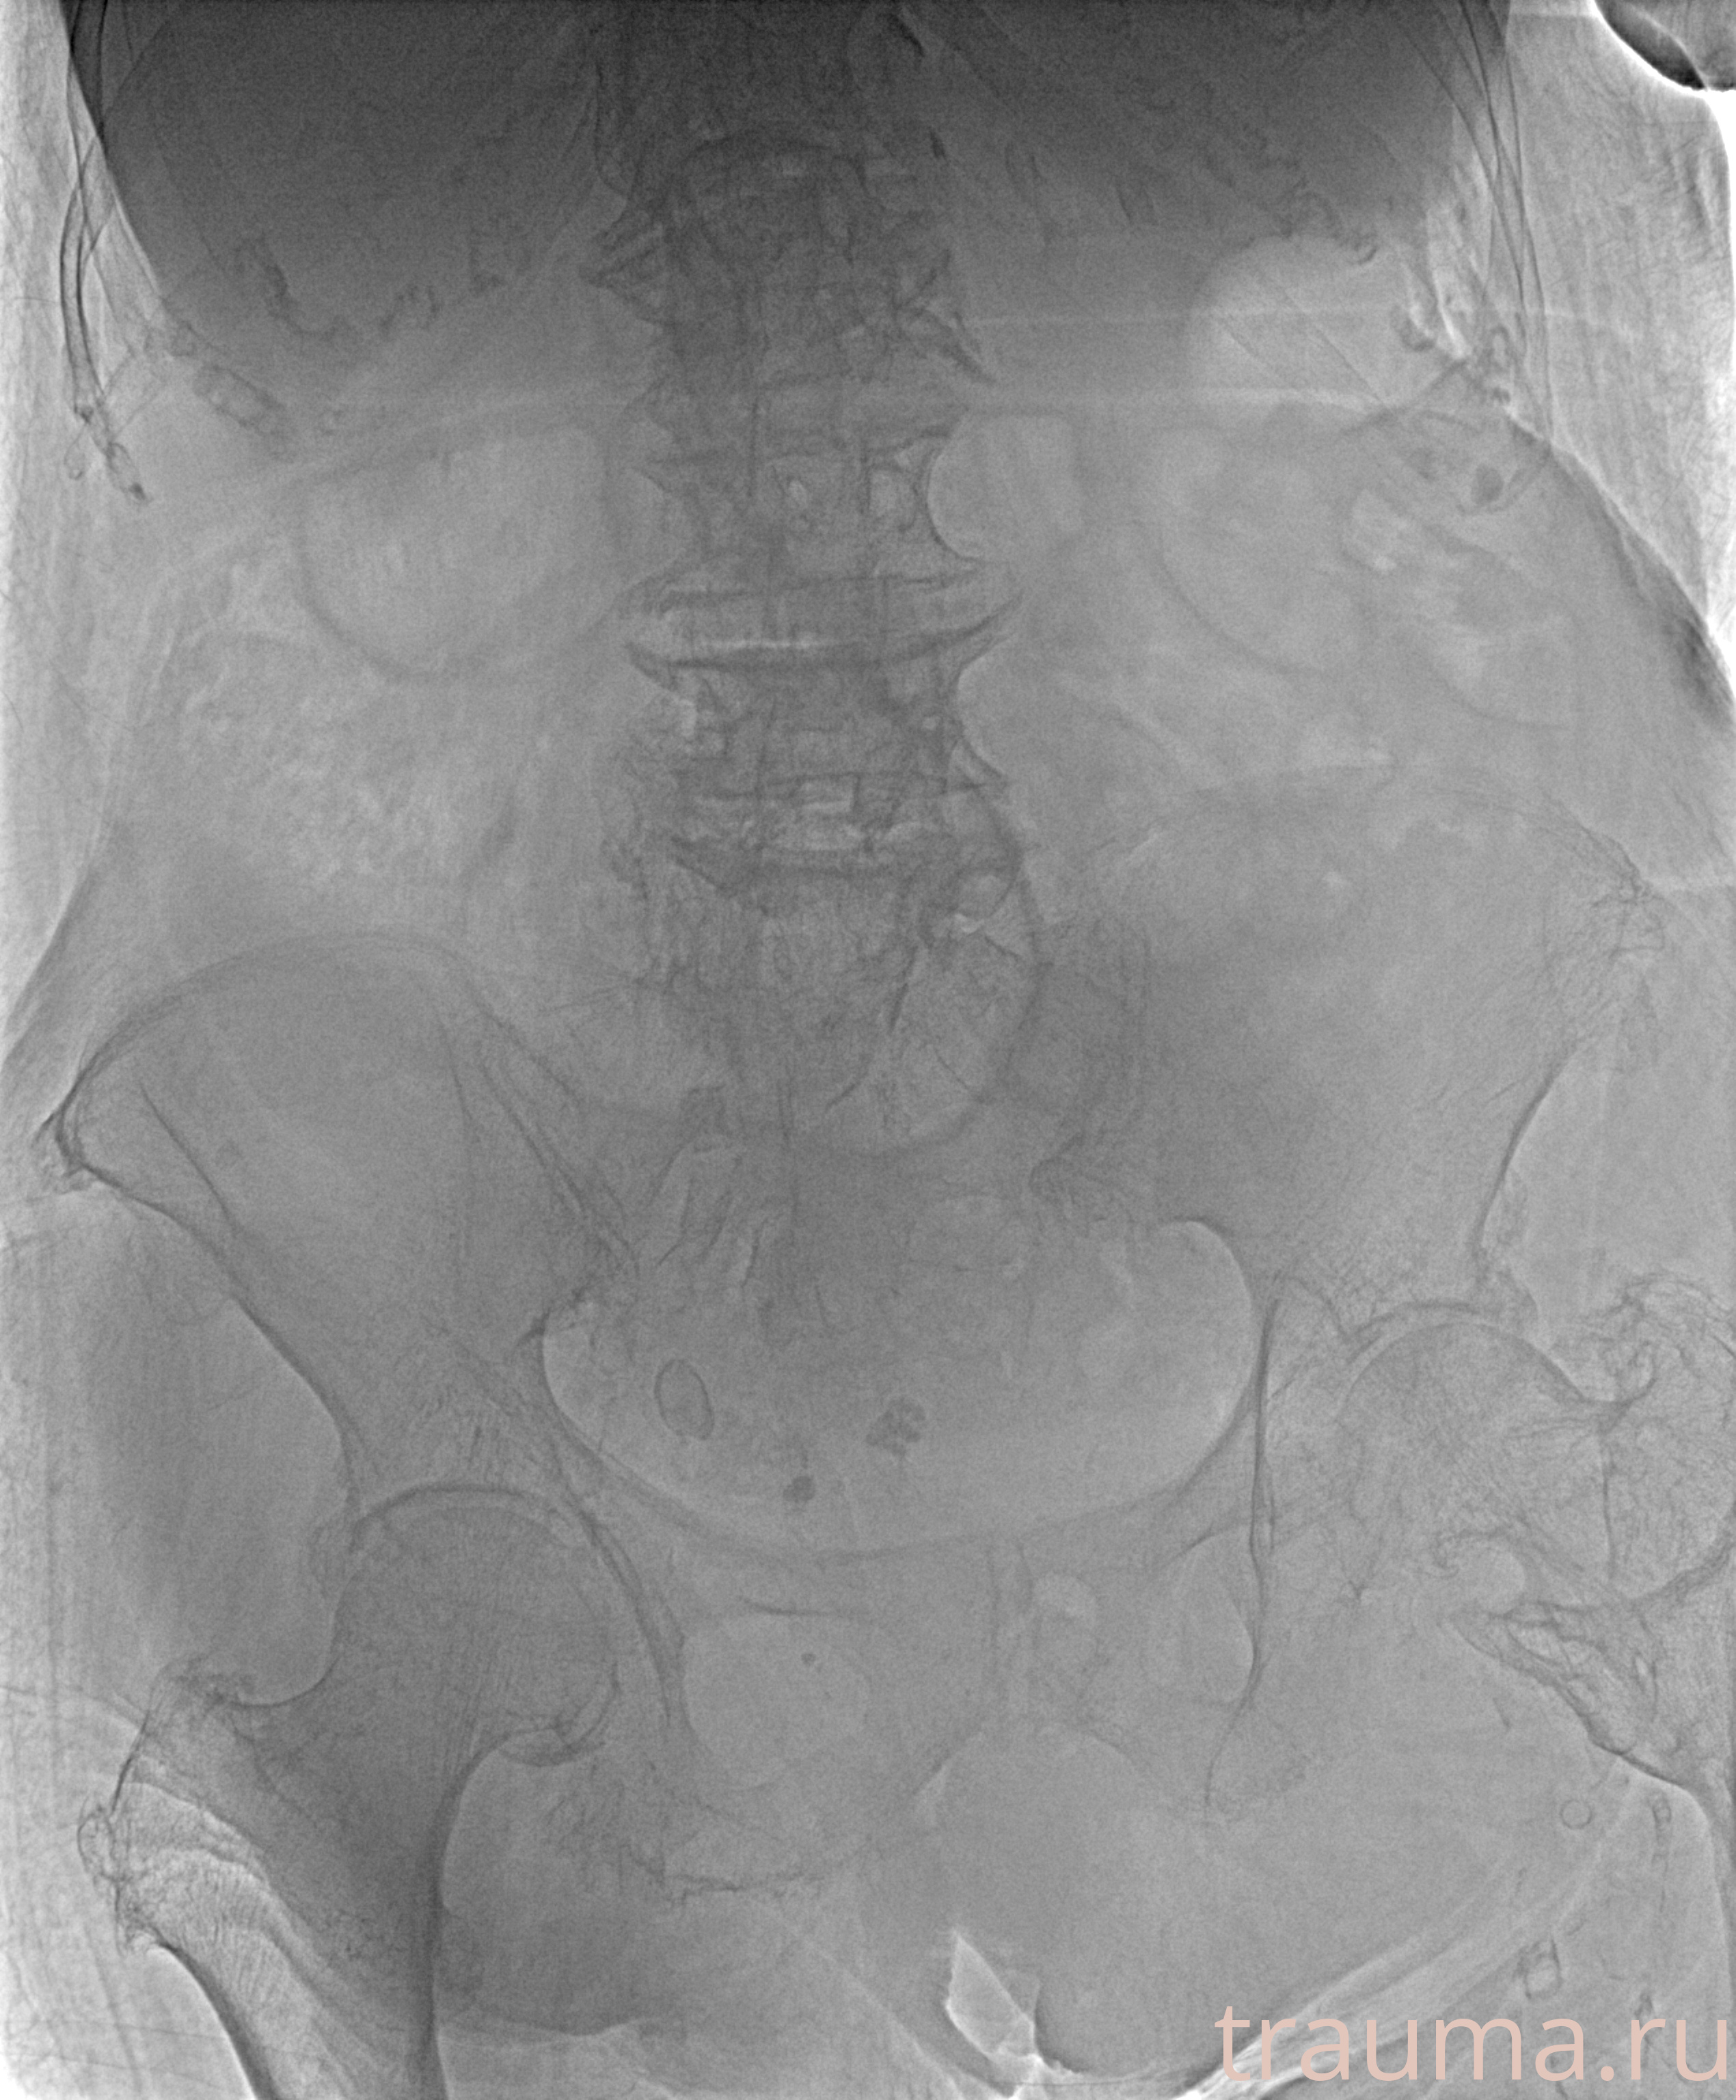

Рентген на дому: по вашему адресу приезжает врач-рентгенолог, травматолог-ортопед с мобильным рентгеновским аппаратом, проводит диагностику травмы или заболевания, делает необходимые рентгенограммы, дает рекомендации по дальнейшему лечению. Получить качественные снимки в домашних условиях возможно благодаря уникальной методике, разработанной МосРентген Центром для института  Склифосовского

при переломе шейки бедра и пневмонии от компании МосРентген Центр - партнера Института имени Склифосовского